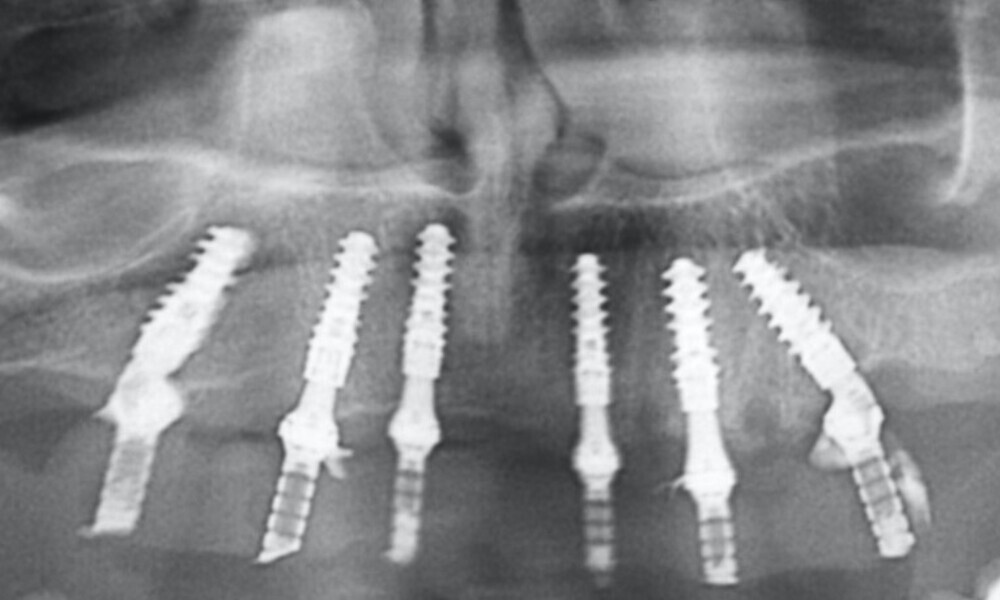

Extra-oral examination showed no significant abnormalities. The patient presented with a medium smile line (Figs. 1–3). The intra-oral examination revealed a fixed bridge spanning teeth #23–26 to which the removable metal partial denture attached (Fig. 4). Teeth #22–17 had been extracted a long time before, and the ridge in this region had healed. No plaque or inflammation was observed. The teeth exhibited mild to moderate attachment loss, but no endodontic or periodontic lesions or root fractures were observed (Figs. 5–8). Analysis of the panoramic radiograph indicated sufficient vertical and horizontal bone availability and adequate bone quality; therefore, there was no need for guided bone regeneration (Fig. 9). According to the International Team for Implantology’s SAC classification, the case was categorised as advanced to complex.

The fit of the previously sterilised provisional guide and surgical guide was then verified (Figs. 21 & 22). The surgical guide was positioned, aligning it with the arch and extraction sockets. Subsequently, the holes for the anchor pins were drilled and the pins inserted (Figs. 23 & 24). The surgery was initiated using a mucosa punch at 15 rpm through the sleeves of the surgical guide. This method allowed for blade-free incision with minimal trauma (Figs. 25 & 26). After removing the mucosal punch, the surgical guide was reinserted to begin the placement of the implants (Fig. 27). The surgical protocol, provided alongside the surgical guide, recommended the sequence of instruments required to prepare each implant site. The osteotomy sites were prepared following the manufacturer’s recommended drilling protocol using a copious amount of saline irrigation, and the implants placed as follows and parallelism checked (Figs. 28–31):

• position #16: 5 × 12.0 mm; regular base (RB);

• position #14: 0 × 12.0 mm; RB;

• position #12: 0 × 12.0 mm; RB;

• position #22: 0 × 12.0 mm; RB;

• position #24: 5 × 12.0 mm; RB; and

• position #26: 5 × 12.0 mm; RB.

Employing a fully guided surgical protocol alongside a completely digital prosthetic workflow allowed for the precise design and milling of a PMMA provisional prosthesis (Figs. 34 & 35). The implant loading protocol implemented was immediate loading with equal distribution of forces across the entire prosthesis. The patient received the screw-retained provisional prosthesis on the same day. Temporary abutments (titanium copings) were placed on top of the screw-retained abutments. The spaces between the titanium copings and the provisional prosthesis were filled (Figs. 36–38). Any excess material was cut away, and the provisional prosthesis was subsequently polished to ensure a smooth finish (Fig. 39). The provisional prosthesis was then attached and securely fixed to the titanium copings to a 15 N cm torque (Fig. 40). Oral hygiene instructions were provided, and the occlusion was assessed (Figs. 41 & 42). A final control radiograph was obtained and confirmed that all parameters were within normal limits (Fig. 43).

The delivery of the final prosthesis was then performed, and the aesthetics, occlusion and function were verified (Figs. 51–55). The panoramic control radiograph showed that all measurements were within expected ranges (Fig. 56).